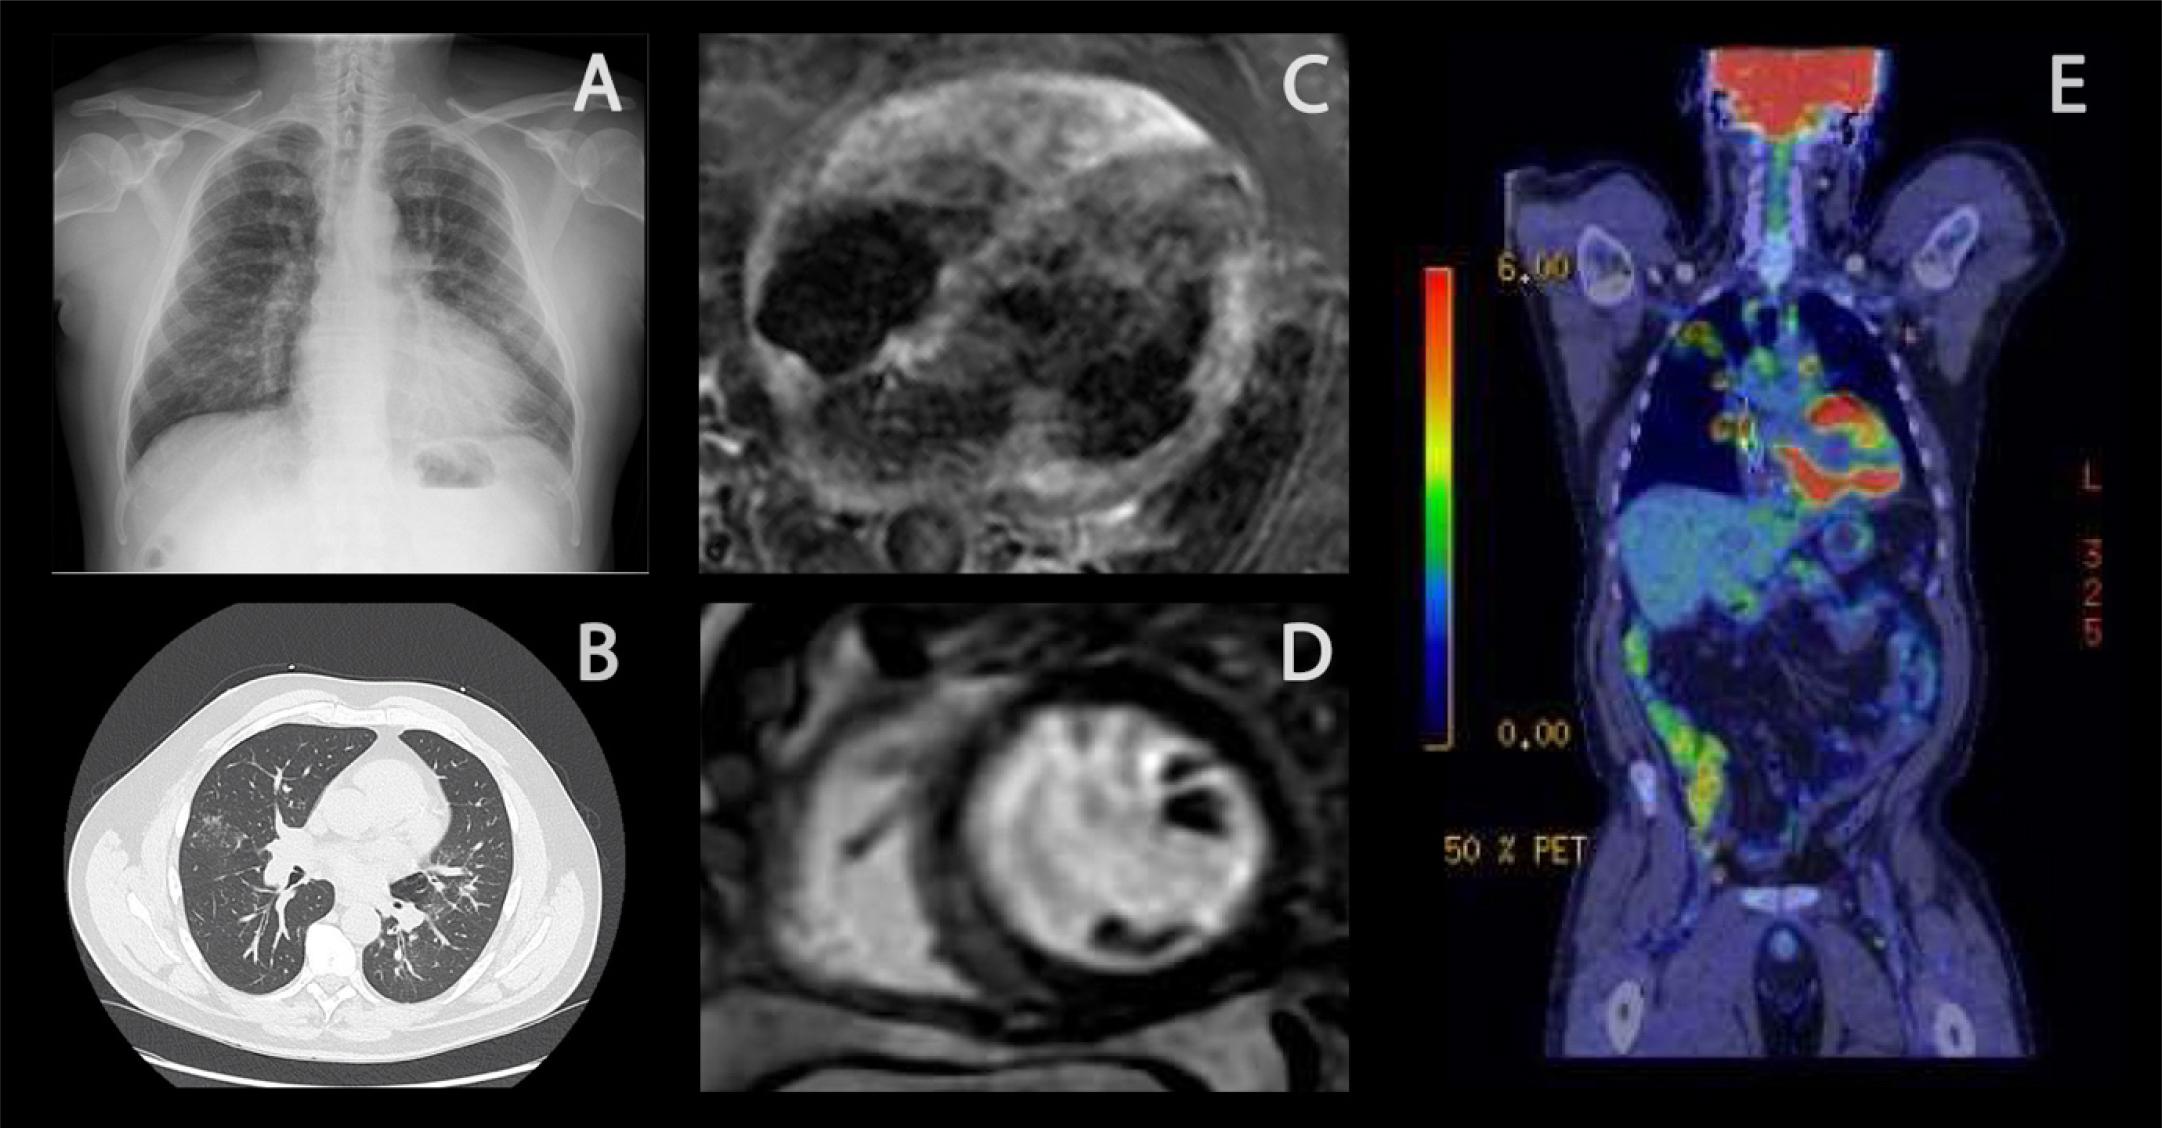

(A) CXR showing bilateral hilar lymphadenopathy. (B) HRCT with micronodules with a perilymphatic distribution, resulting of discrete, confluent, or cluster distribution. (C) Triple IR (oedema) imaging demonstrating multiple areas of increased myocardial signal. (D) Gadolinium study demonstrating multiple subepicardial and mid-myocardial areas of LGE (E) FDG-PET CT with apical pulmonary infiltrates and hilar lymph node involvement and extensive lymphadenopathy from the cervical area to the retroperitoneum. Markedly increased uptake in myocardium and nodular moderate uptake in the splenic parenchyma indicative of extensive active sarcoidosis with cardiac involvement. CXR, Chest radiography; HRCT, High-resolution computed tomography; LGE, Late gadolinium enhancement; FDG-PET CT, Fluorodeoxyglucose-positron emission tomography.